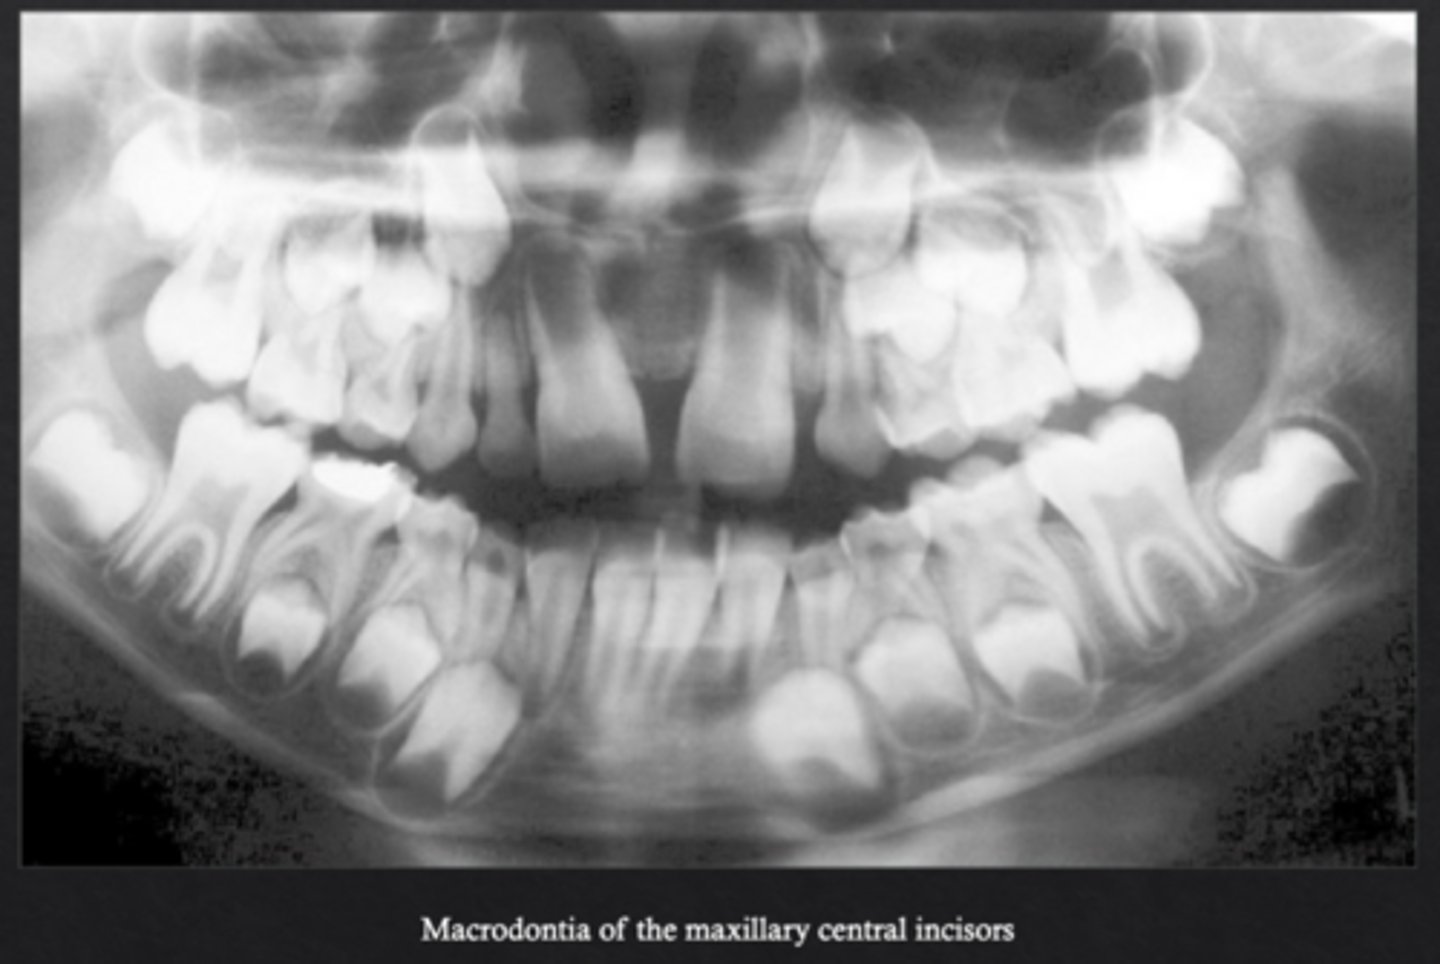

What is macrodontia?

Teeth are larger than normal *may be syndrome associated